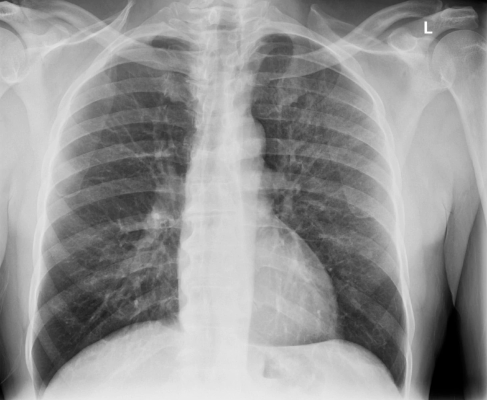

Chest with AI Brightness and Contrast (AIBC), using Helix 2.2 Advanced Imaging Processing.

Cutting-edge 100 um FlashPad HD detectors and the latest Helix 2.2 advanced image processing with on-device artificial intelligence (AI) provides outstanding clarity and exceptional anatomical detail across image types with anatomy-specific image enhancement regardless of variations in dose, patient positioning, field of view and metal.